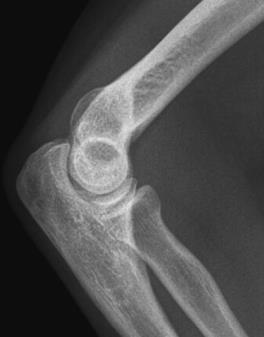

Świadczenie usług medycznych …

W ułożeniu do rentgenografii AP stawu kolanowego promień główny pada

A. prostopadle na podstawę rzepki.

B. pod kątem 30° na podstawę rzepki.

C. pod kątem 30° na wierzchołek rzepki.

D. prostopadle na wierzchołek rzepki.